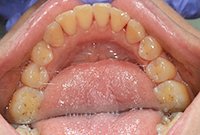

Изменения тканей, которые окружают корни зубов, к сожалению, неизбежны и с возрастом наблюдаются у всех, однако в разном объеме. Так, на развитие пародонтита влияет болезнетворная микрофлора полости рта, которая есть у каждого из нас, но на мы в силах повлиять на ее количество.

Сохранить зубы и пародонт помогает правильная гигиена полости рта дома и в кресле стоматолога, а также своевременное протезирование и имплантация, которые замещают удаленные зубы и равномерно распределяют жевательную нагрузку, не позволяя костной ткани атрофироваться.

Таким образом, по мнению стоматологов, риск возникновения болезней десен на 80% зависит от сознательности самого пациента.